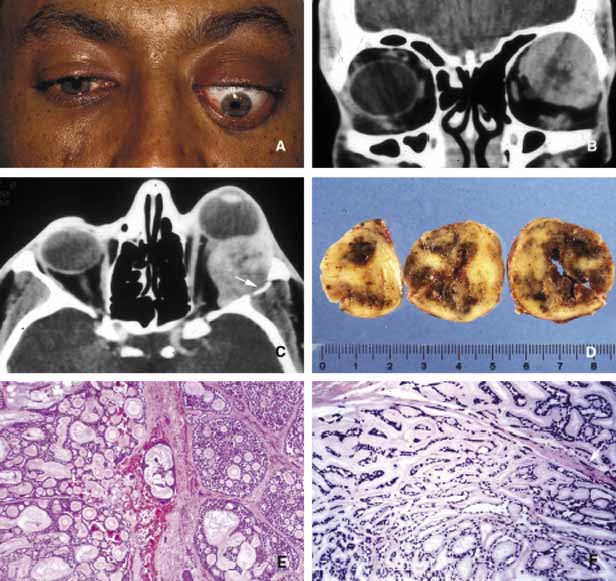

Primary epithelial neoplasms of the orbit originate from the ductal and acinar epithelium of the lacrimal gland.167,168 The most commonly encountered lacrimal gland tumor is pleomorphic adenoma (benign mixed tumor) (BMT). This neoplasm is known as a “mixed” tumor because it is composed of a mixture of epithelial and stromal elements (Fig. 14). The epithelial elements of the tumor consist of glandular and ductal formations that may develop squamous metaplasia and small keratin filled cysts. The stroma is composed of myxoid tissue that may contain cartilage and bone. In most cases the BMT of the lacrimal gland is multilobulated and surrounded by a fibrous capsule. If additional smaller lobules are present in the vicinity of the main lesion, these satellite nodules are individually encapsulated as well. When malignancy develops within a BMT it is classified according to its predominant histopathologic component as adenocarcinoma within pleomorphic adenoma, adenoid cystic carcinoma, or poorly differentiated carcinoma. Malignant transformation may happen as a rapid growth within an unknown tumor or may take place decades after diagnosis of the BMT.169 Adenoid cystic carcinoma, the most common malignant tumor of the lacrimal gland may also develop de novo. This is a highly malignant neoplasm that can be seen in adolescents and may develop rapid extension into the adjacent structures including the cranium by direct invasion and to the base of the skull by painful perineural invasion.170,171 The histopathologic appearance of adenoid cystic carcinoma may present as several variants including the most common “Swiss cheese” pattern that consists of cribriform clustering of small basophilic tumor cells surounded by thick basement membrane (Fig. 15). Other types including diffuse basaloid, sclerosing, tubular, and comedocarcinoma are known to exist.172

Fig. 14 Benign mixed tumor (BMT). Coronal CT (A) depicts a well-delineated mass in the superior lateral orbit causing inferior medial dislocation of the globe. Frame B shows multilobulated nature of pleomorphic ademona (benign mixed tumor). The tumor nodules are bisected to show the encapsulation and the focal nature of the tumor masses; the nodule on the right was discovered inferior to the main lesion as a satellite mass (B). Histopathologically pleomorphic adenoma is composed of a mixture of glandular (g) and myxoid (m) tissues (C, D). Some of the glandular formations may develop squamous metaplasia and distend to form cystic space (c) secondary to keratin accumulation. (D)

Fig. 15 Adenoid cystic carcinoma. A large superior temporal mass causing marked proptosis of the eye and inferior displacement (A, B, C). The axial CT scan depicts the infiltration of the lateral wall with the tumor (arrow) (C). Serial sectioning of the tumor showing focal areas of hemorrhagic necrosis and cystic changes (D). Frames E and F depict the histopathological appearance of adenoid cystic carcinoma forming a “Swiss cheese” pattern with proliferation of atypical, irregular, glandular structures. Peripheral nerve sheath involvement (arrow) is seen in frame F.

Both benign and malignant tumors of the lacrimal gland present with proptosis and inferior medial displacement of the globe that can readily be demonstrated on CT and MRI studies showing cavitation of the lacrimal fossa in chronic benign lesions and direct invasion of the bony tissues in malignant tumors. Adenocarcinoma developing in BMT (pleomorphic adenocarcinoma, malignant mixed tumor) presents with atypical features within tubular and glandular structures.169 Mucoepidermoid carcinoma of the lacrimal gland consists of diffuse proliferation of atypical squamous cells with abundant vacuolated cytoplasm containing mucin. The clinical course of mucoepidermoid carcinoma is chronic with a relatively favorable prognosis.173,174 Other than true neoplasms, cystic dilatation of the lacrimal gland ductules that is known as dacryops and ectopic lacrimal gland tissue presenting in areas away from the anatomic site of the gland also present as space occupying lesions in the lacrimal fossa.175–177